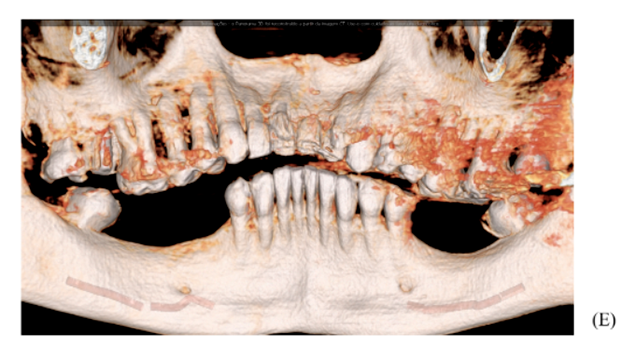

Figuras 1 e 2 – Visão intrabucal da paciente, evidenciando instabilidade da prótese fixa de resina, bem como sua deficiência estética.